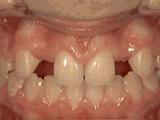

第三种

前牙移位,因为有牙齿缺失,导致相邻牙齿开始没有秩序的乱移动,经过矫正后是这样的~